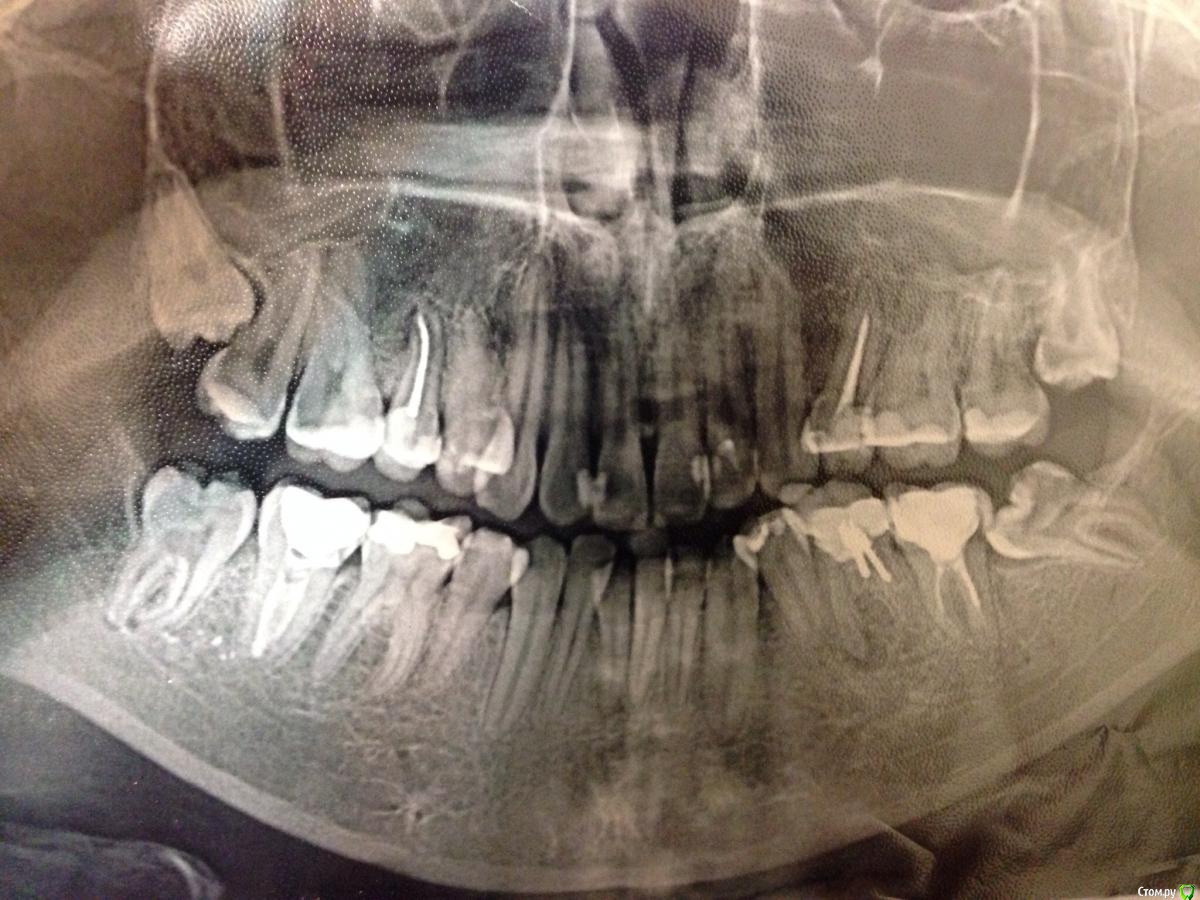

Thend Опубликовано 17 февраля, 2015 Поделиться Опубликовано 17 февраля, 2015 (изменено) Здравствуйте! У меня вопрос по 6, 7 и 8 слева снизу. Стоит ли пытаться лечить 6? Несколько врачей сказали мне попытаться пройти каналы, положить лекарство и ждать что будет. Другие что лечению не подлежит и лучше его удалять. Какие могут быть последствия если не удалить сейчас? Штифт ставился год назад из за того что стенка зуба откололась, а канал видимо залечить не смогли. Про семерку сказали что каналы не до конца пролечены, стоит ли из перелечивать сейчас? Семерку мне нужно сохранить так как соседние зубы кажется рано или поздно будут удалены. И насчет восьмерки, там огромная кариозная дыра, но после консультации с ортодонтами( тоже разные мнения) восьмерку было решено пока не удалять. Есть ли возможность качественного лечения? Так как опять же разные врачи имеют разные мнения. Пока зубы хочу сохранить до ортодонтического лечения, которое в свою очередь затруднено тем что я учусь в другом городе. Надеюсь на вашу помощь. Изменено 17 февраля, 2015 пользователем Thend Ссылка на комментарий

Thend Опубликовано 17 февраля, 2015 Автор Поделиться Опубликовано 17 февраля, 2015 Да, забыла. Снимок, к сожалению, только такой. Ссылка на комментарий